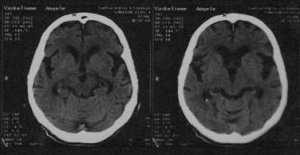

Galvos

smegenų KT- smilkininių ir kaktinių skilčių atrofija (išorinė

ir vidinė hidrocefalija).